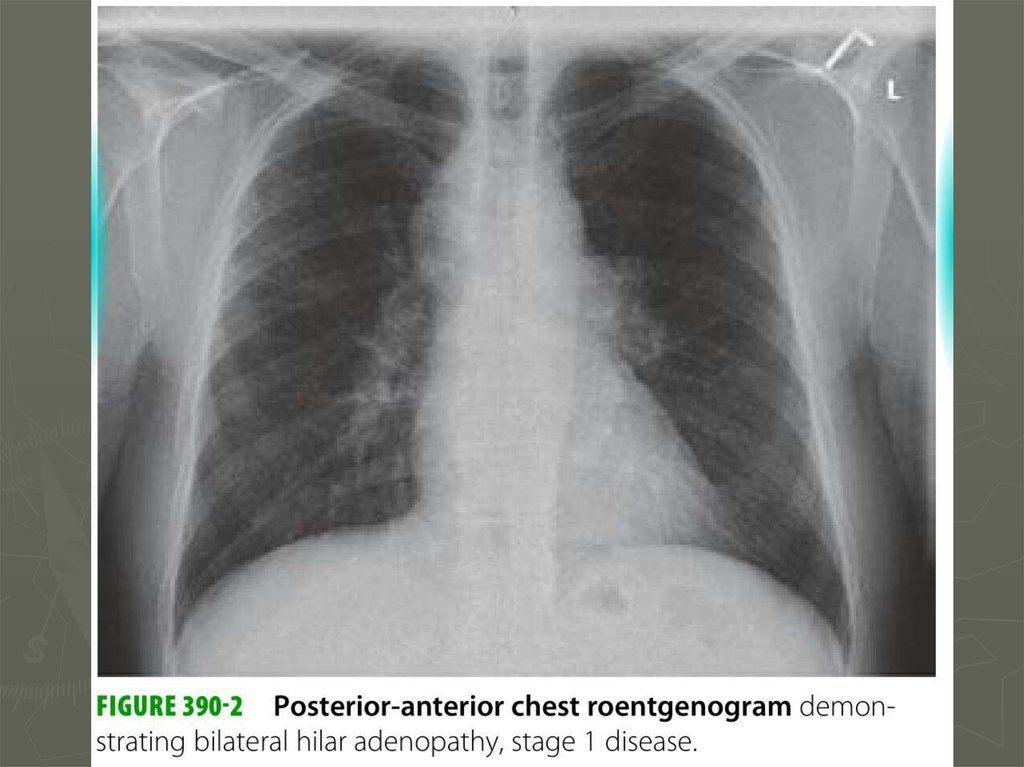

10. Диагностика

11. Диагностика